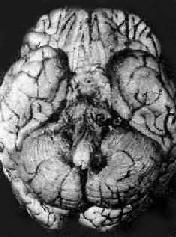

病理变化以脑底最明显。在脑桥、脚间池、视神经交叉及大脑外侧裂等处之蛛网膜下腔内,有多量灰黄色混浊胶冻样渗出物积聚。偶见比粟粒还小的灰白色结核结节(图18-14)。脑室脉络丛及室管膜有时也可有结核结节形成。镜下,蛛网膜下腔内炎性渗出物主要由浆液、纤维素、巨噬细胞、淋巴细胞组成,常有干酪样坏死,偶见典型结核结节形成。病变严重者可累及脑皮质而引起脑膜脑炎。病程较长则可发生闭塞性血管内膜炎,从而可引起多发性脑软化。未经适当治疗致病程迁延的病例,由于蛛网膜下腔渗出物的机化而发生蛛网膜粘连,可使第四脑室上中孔和外侧孔堵塞,引起脑积水。

图18-14 结核性脑膜炎

脑基底部脑膜增厚,有散在的结核结节